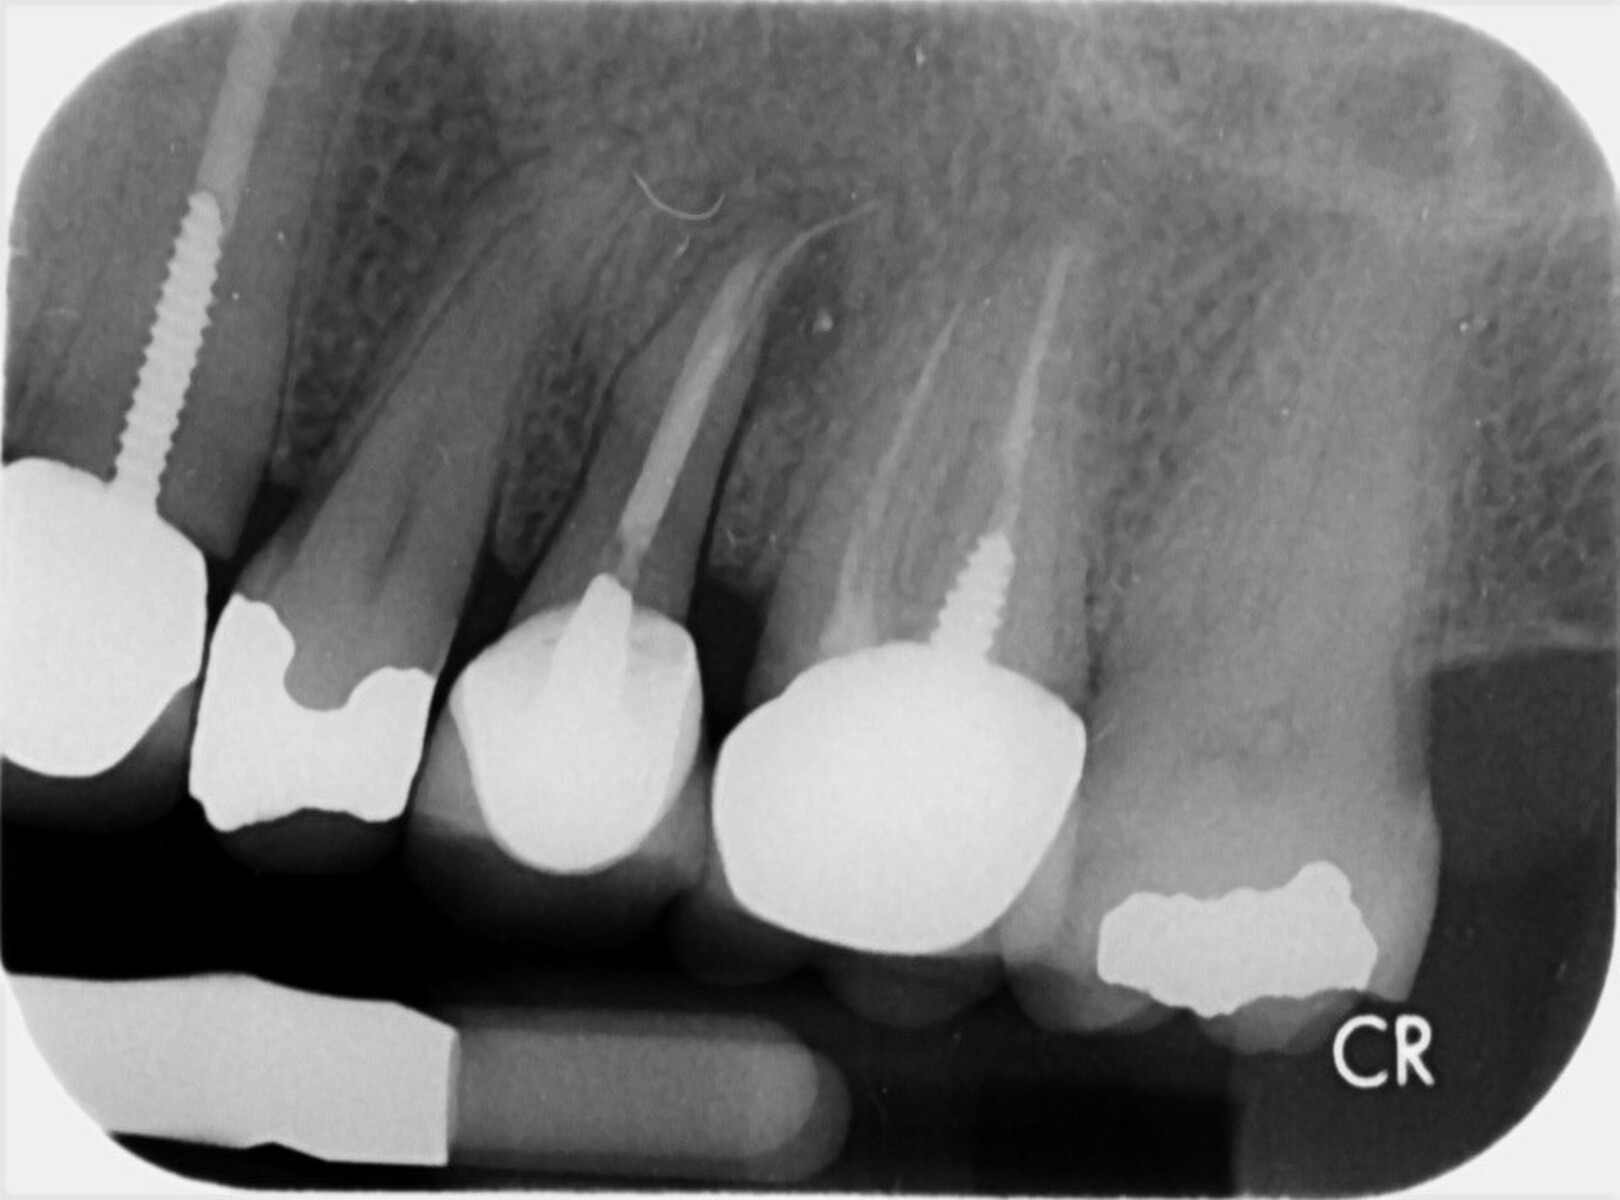

(PDF) Mandibular First Premolars With Bifurcated Root and Two canals Bifurcated Root  A bifurcation is a juncture of two roots at the base of a tooth, which can be affected by bone loss and periodontal disease. Find out the causes, symptoms, diagnosis and prognosis of furcation involvement of a dental infection. Mandibular first premolars may also exhibit a bifurcated root, one buccal, and one lingual (fig. Learn what bifurcation and trifurcation are. Bifurcated Root.

Vertical Root Fracture in Buccal Roots of Bifurcated Maxillary Bifurcated Root  A bifurcation is a juncture of two roots at the base of a tooth, which can be affected by bone loss and periodontal disease. Mandibular first premolars may also exhibit a bifurcated root, one buccal, and one lingual (fig. This chapter reviews the external and internal morphology of roots and canals, and introduces a new coding system for classifying. Find. Bifurcated Root.

Buccal root of the bifurcated maxillary premolar—a danger zone during Bifurcated Root  Find out the causes, symptoms, diagnosis and prognosis of furcation involvement of a dental infection. Mandibular first premolars may also exhibit a bifurcated root, one buccal, and one lingual (fig. The mandibular first and second premolars typically present with single roots but may have bifurcated roots in rare situations. A bifurcation is a juncture of two roots at the base. Bifurcated Root.

Buccal root of the bifurcated maxillary premolar—a danger zone during Bifurcated Root  The mandibular first and second premolars typically present with single roots but may have bifurcated roots in rare situations. Mandibular first premolars may also exhibit a bifurcated root, one buccal, and one lingual (fig. This chapter reviews the external and internal morphology of roots and canals, and introduces a new coding system for classifying. Which of the following premolar teeth. Bifurcated Root.

Buccal root of the bifurcated maxillary premolar—a danger zone during Bifurcated Root  Mandibular first premolars may also exhibit a bifurcated root, one buccal, and one lingual (fig. Which of the following premolar teeth normally has a bifurcated root? Learn what bifurcation and trifurcation are in a tooth, how they affect the root structure and the surrounding bone, and how to treat them. Find out the causes, symptoms, diagnosis and prognosis of furcation. Bifurcated Root.

Buccal root of the bifurcated maxillary premolar—a danger zone during Bifurcated Root  Mandibular first premolars may also exhibit a bifurcated root, one buccal, and one lingual (fig. Which of the following premolar teeth normally has a bifurcated root? This chapter reviews the external and internal morphology of roots and canals, and introduces a new coding system for classifying. The mandibular first and second premolars typically present with single roots but may have. Bifurcated Root.